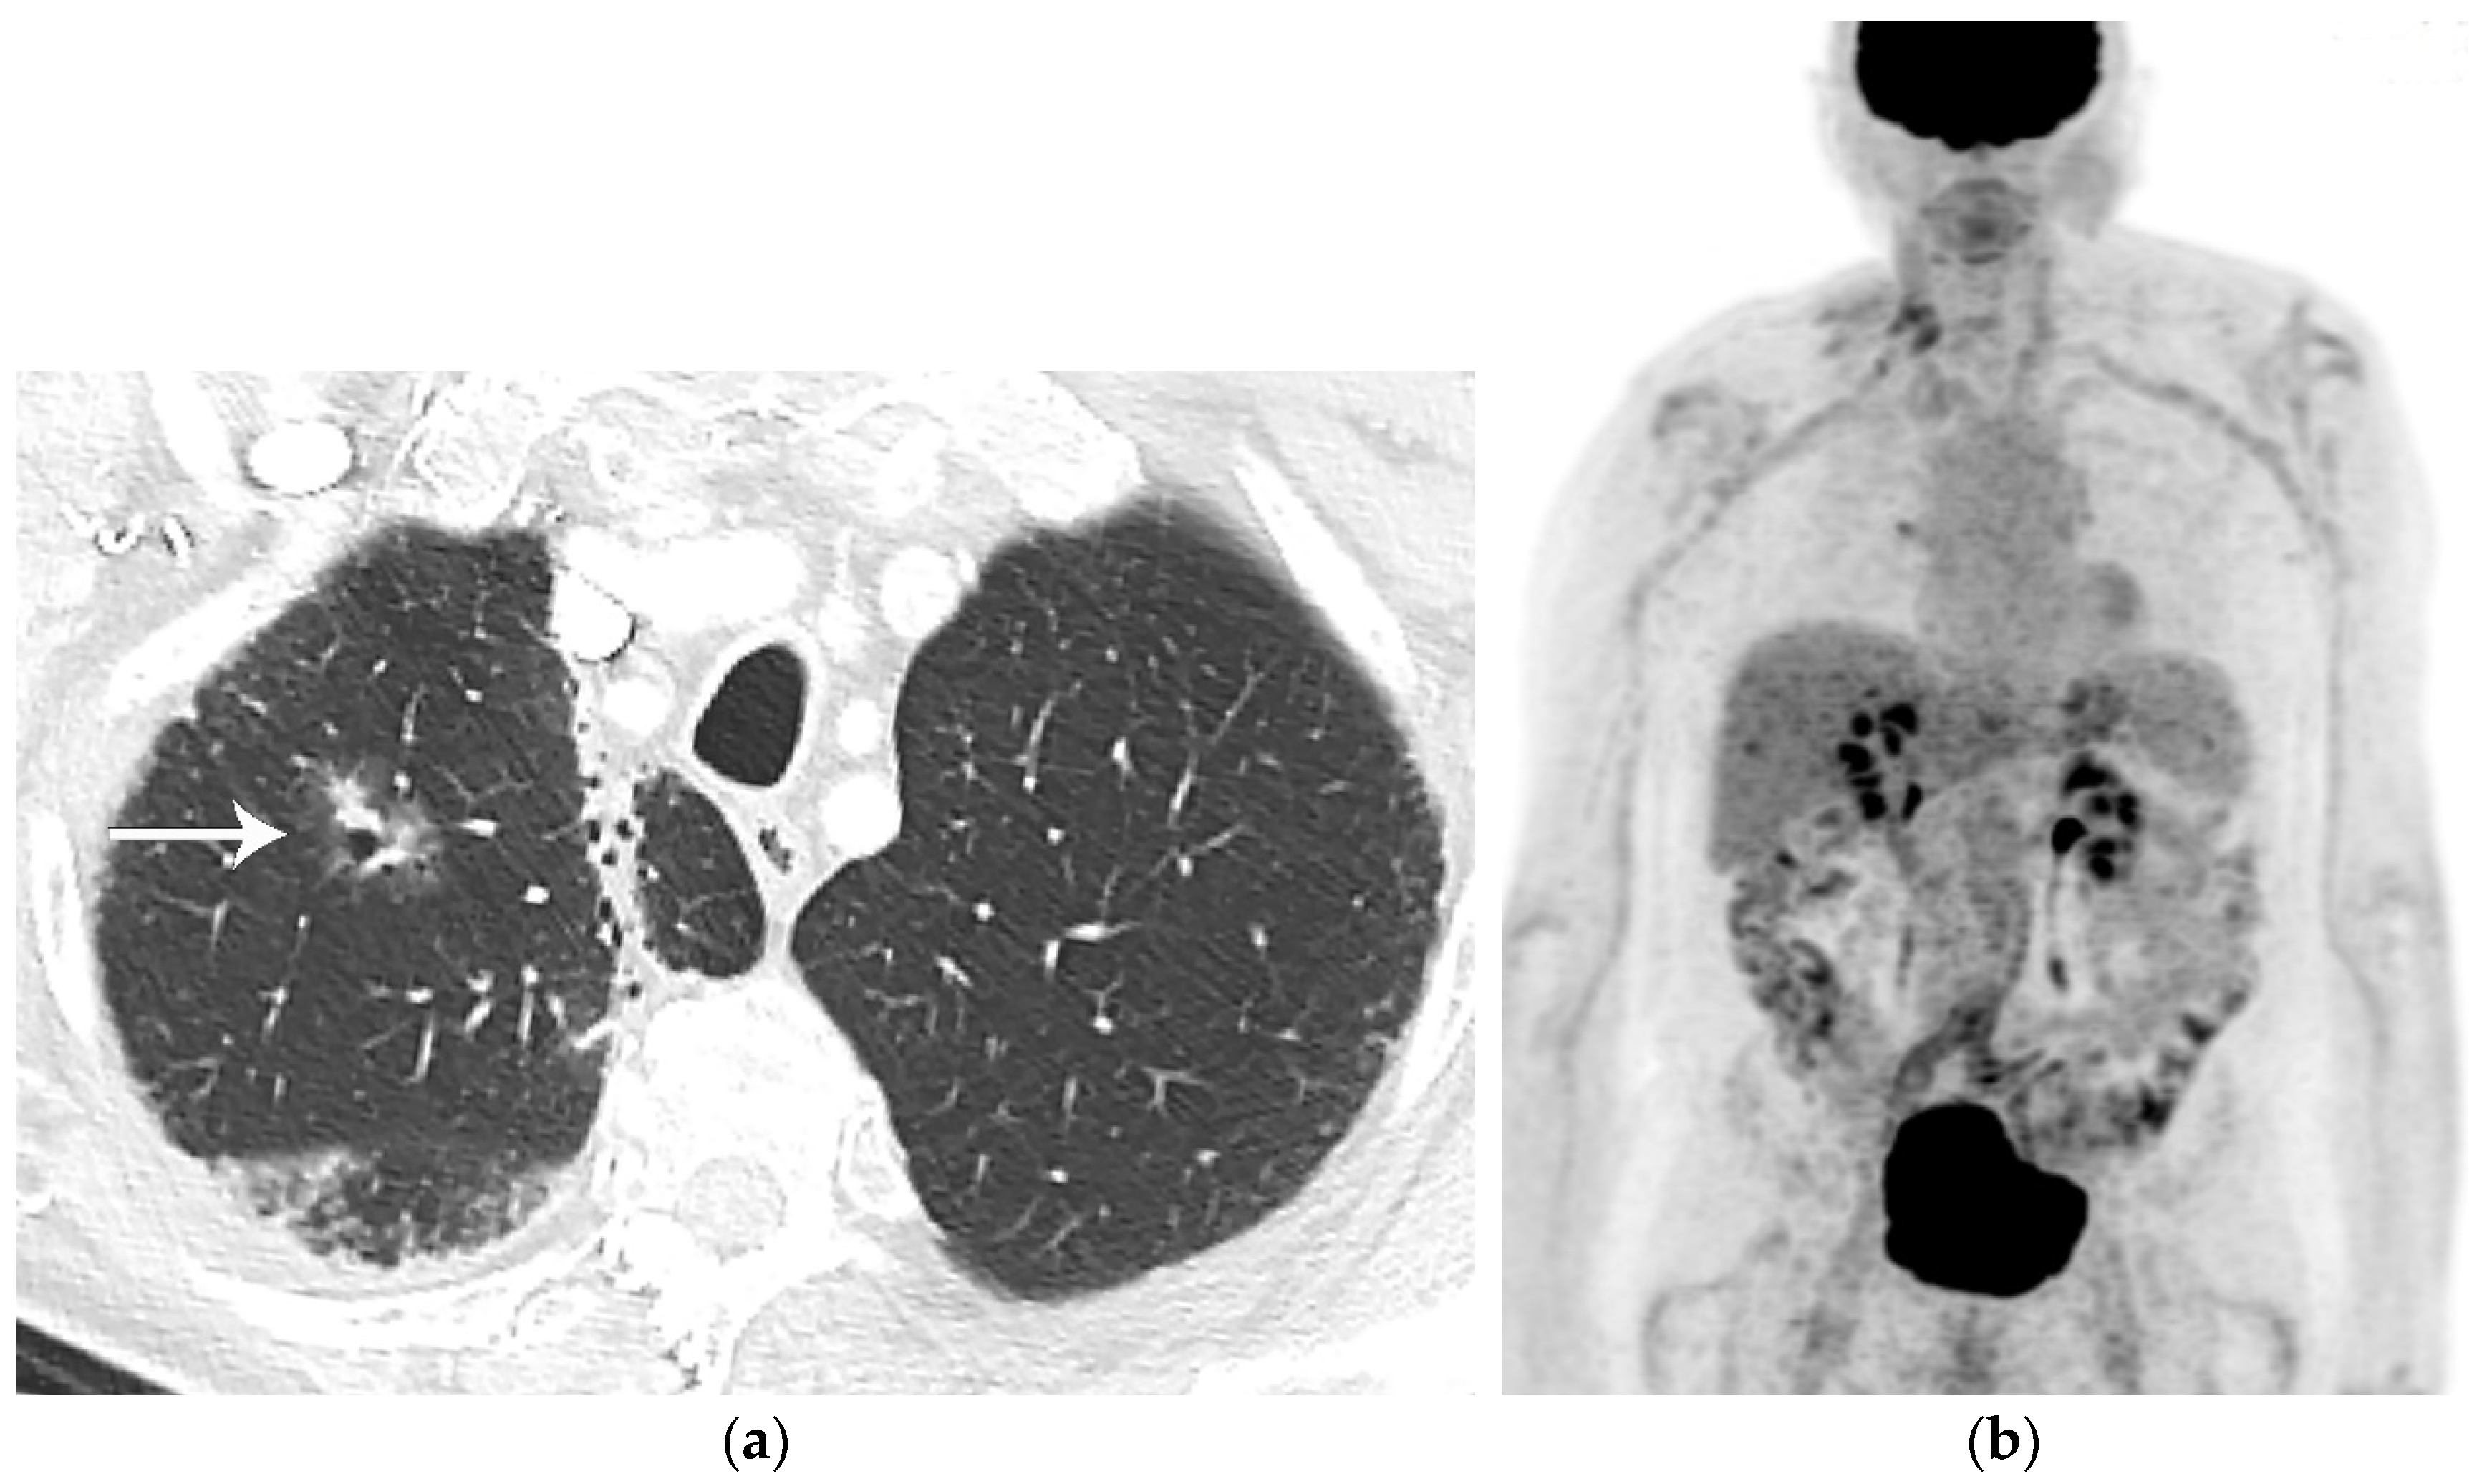

6. PET/CT for Lung Cancer